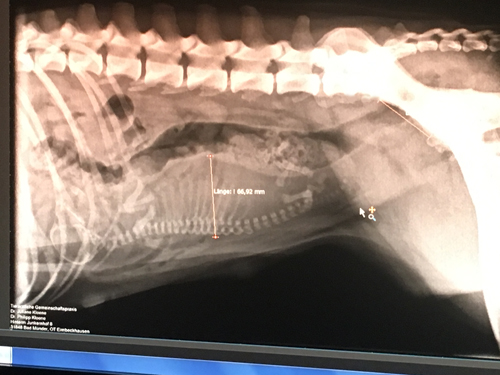

Wir wussten, dass es nur ein Welpe wird und Isabell war in enger tierärztlicher Kontrolle.

Die Entscheidung zum Kaiserschnitt, wurde von zwei Tierärzten entschieden, um Isabell und den Kleinen nicht zu gefährden, da Naruto schon sehr groß war.

Röntgen IMG_8112 klein